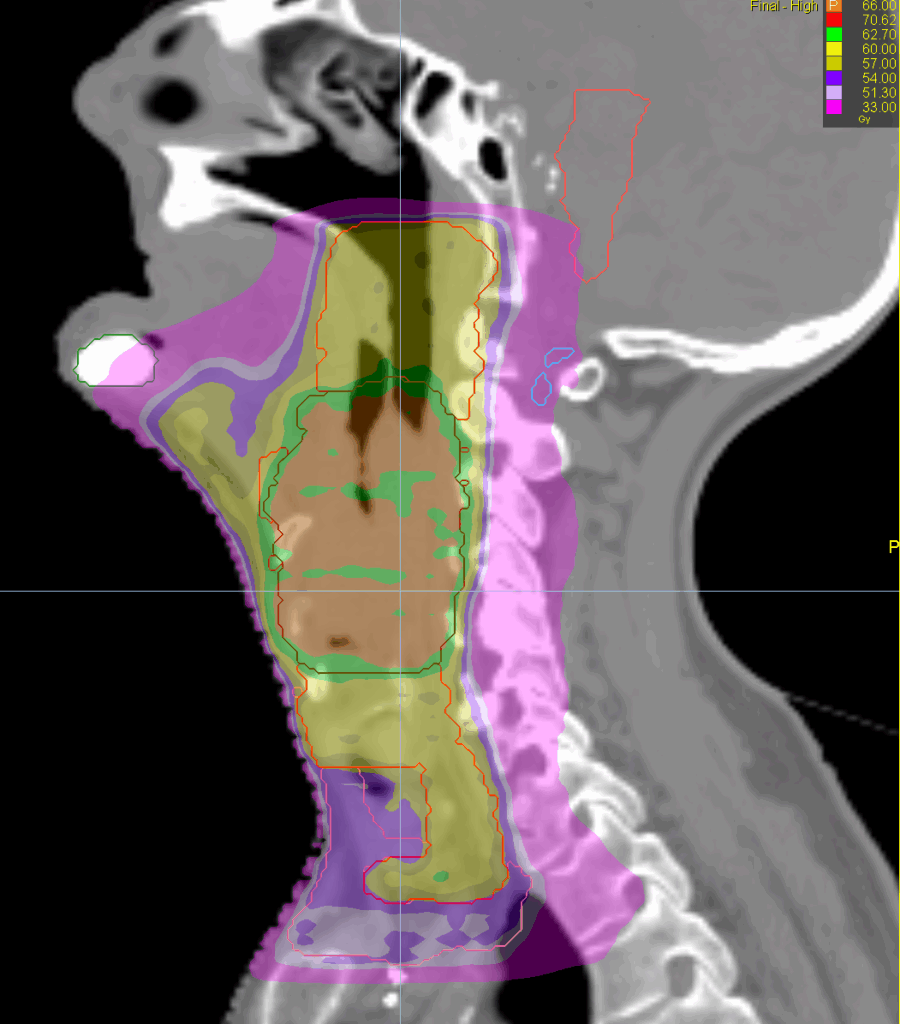

Treatment Plan Images

Fractionation / Protocol Used

66/60/54 Gy in 33 fractions

- TomoHelical™ 2.5 cm